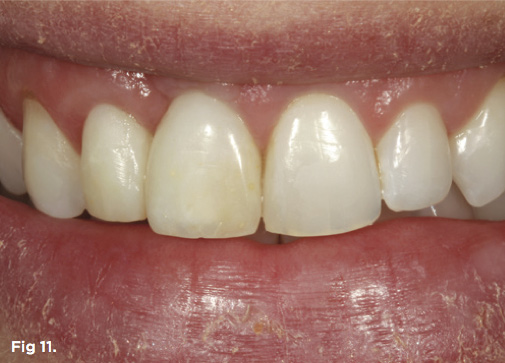

After 6 months of healing of the implant, stage 2 uncovering was performed and the mucosal tissues were allowed to mature for another 2 to 3 weeks. A temporary screw-retained implant cylinder was joined to the implant and acrylic crown (Figure 8). The subgingival shape of the temporary was modified with additional acrylic and the technique of non-surgical tissue sculpting, which was developed to provide the proper emergence profile to the mucosal tissues.27 It is important that the temporary blanching (ischemia) of the mucosal tissues dissipate after 10 minutes (Figure 9). After 3 weeks, soft-tissue scalloping through gingivectomy was done to recreate the proper shape (ie, gingival zenith)28 and proportion for the mucosal tissues (Figure 10). Fiberotomy on the distal aspect of tooth No. 7 was not performed during treatment; therefore, this papilla was slightly more incisal (longer) than the adjacent papillae (Figure 11). A final impression was made of crown No. 7 and implant No. 8 at the implant level to enable a working cast to be made in the laboratory. An all-ceramic custom abutment was made for implant No. 8, and splinted full-coverage units were made for crowns No. 7 and No. 829 (Figure 12). The custom abutment was seated intraorally and torqued according to the manufacturer’s recommendation. The crowns were luted with provisional cement and maintained at 4-month recall intervals (Figure 13). Note the health of the periodontal tissues and its integration with the adjacent teeth and surrounding gingiva, taking a complex esthetic and functional problem for a patient with a high smile line and providing a predictable restorative and esthetic outcome (Figure 14).

Fig 11. The smile of the patient in provisional restorations tooth No. 7 and implant No. 8 after correction and healing of the periodontium.

Figure 11